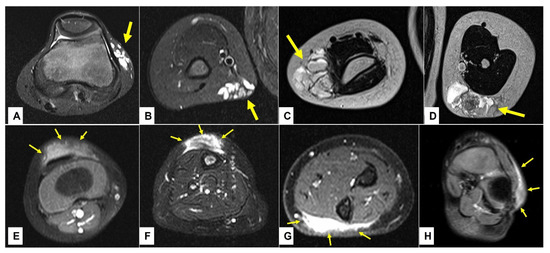

Figure 9.

This composite figure illustrates the typical imaging differences between the low-flow subcutaneous vascular malformations (SVM) and subcutaneous granuloma annulare (SGA) as seen on the MR images. In images (A–D), four patients with multicystic subcutaneous lesions pointed out by yellow arrows are presented. These lesions were accurately diagnosed by MRI and after excision, also confirmed by histopathology as a venous malformation on the left knee in an 11-year-old boy (A); venous malformation on the right upper arm in a 4-year-old boy (B); lymphatic malformation on the right elbow in a 4-year-old girl (C); lymphatic malformation on the left upper arm in an 8-year-old girl (D). In images (E–H), four patients with homogenous subcutaneous lesions marked with 3 yellow arrows each are presented. These lesions remained inconclusive after MRI, with the main differential diagnosis being the low-flow SVM in all cases. Because malignancy could not be excluded, surgical biopsy was needed, and the diagnosis of SGA was confirmed by histopathology in all cases. (E) right knee in a 2.5-year-old boy, (F) right lower leg in a 3-year-old girl, (G) left forearm in a 4-year-old boy, (H) left foot in a 3-year-old girl. Note that all SVM have a cystic appearance on the MRI, whereas SGA shows the typical epifascial extension with gradual rise of the lesion towards the more superficial tissues, which we have named the “epifascial cap” sign. These self-limiting lesions show a homogenous appearance in the MRI and do not invade the fascia.

3.3. Retrospective Image Analysis

A retrospective review of all MR images showed that all MRIs of patients with low-flow SVMs showed multicystic and/or tubular lesion appearance, whereas MRIs of patients with SGA never showed any cyst-shaped structures. An SGA presents as a raised-rounded homogenous mass that projects over the surface of the muscle’s fascia without invading the underlying tissue (Figure 9). These lesions have a typical broad circular base laying on the fascia and a raised, continuous, irregular curved surface that extends from the deep fascia towards the more superficial tissues. One can easily describe the shape of an SGA as an island rising from the ocean. We recently named this characteristic shape “the Epifascial Cap,” the hallmark shape of an SGA (Figure 10) []. The enhancement of contrast material seen in these lesions during the MRI is homogenous and should not be mistaken for a low-flow SVM (Figure 11).